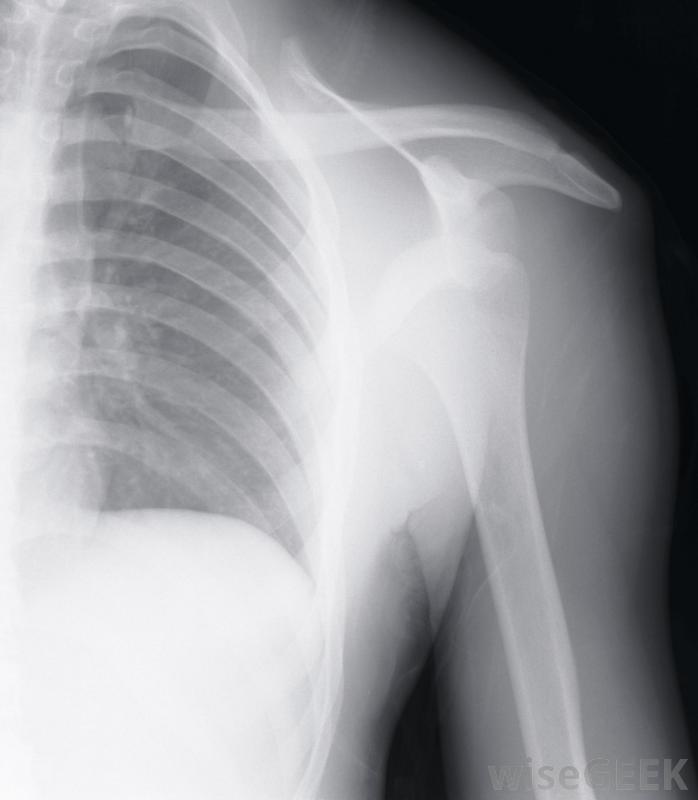

對于側睡的人來說,睡在受影響的肩膀上會加重滑囊炎,因此理想情況下應避免使用。如果休息和結冰不能幫助治愈滑囊炎的疼痛,應尋求醫療幫助。如果肩關節紅腫,應立即尋求專業醫護人員;這通常表明感染。醫生會為感染性肩滑囊炎開抗生素治療醫生也可以進行一些診斷測試,包括血液測試、超聲波掃描或x光檢查。

肩關節x光檢查可幫助指示肩關節滑囊炎的嚴重程度和正確的治療。